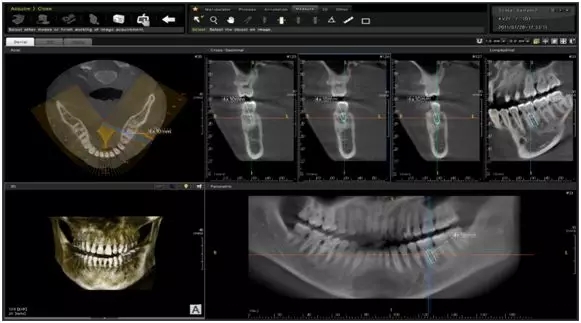

Apsaras 3D CT是康達(dá)洲際自主生產(chǎn)的首款三合一多功能口腔CT,操作簡(jiǎn)單方便。后處理軟件功能豐富多樣,擁有豐富的種植體數(shù)據(jù)庫(kù),及投影測(cè)量分析軟件,此款產(chǎn)品可以滿足口腔科全科所有影像的拍攝,大大滿足了用戶的需求。

01影像質(zhì)量展示

三維影像具備單次掃描:14cm×14cm(底×高)的影像視野,一次拍攝便可以包括雙側(cè)顳頜關(guān)節(jié)影像,高度可超過(guò)上頜竇竇底,影像質(zhì)量?jī)?yōu)異??梢栽谌S影像下得到重建出來(lái)的二維全景片。